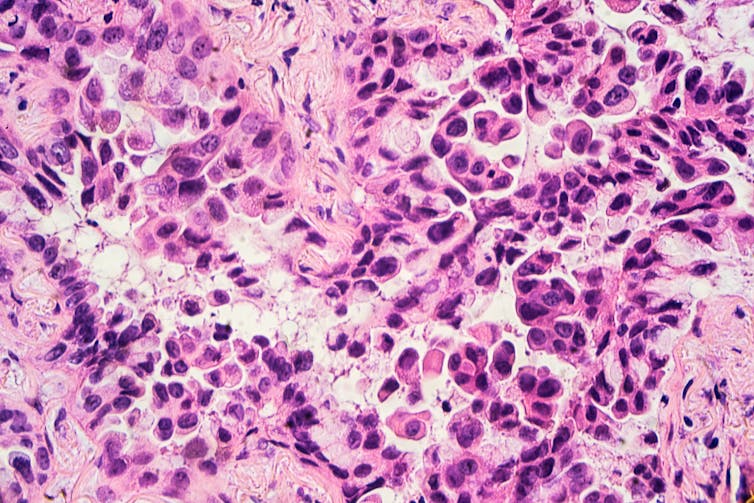

Like any cancer, lung cancer consists of abnormal cells that proliferate in an uncontrolled fashion, do not obey normal signals to die and cannot repair their DNA. Normal lung cells become cancerous through exposure to tobacco smoke, radon gas, asbestos or airborne pollutants.

In recent years, low-dose CT has begun to be used to screen for lung cancer. Regular chest X-rays detect lung cancers only when they measure centimeters in diameter – the size of a penny or bigger – but CT can find them much earlier, when they are only millimeters wide. As with any cancer, early detection is key to improved survival. Unfortunately, once lung cancer causes symptoms – such as persistent cough, coughing up blood, and weight loss – it has already reached an advanced stage. These newer CT scans also use a lower dosage of X-rays, lowering the risk of causing other health problems.